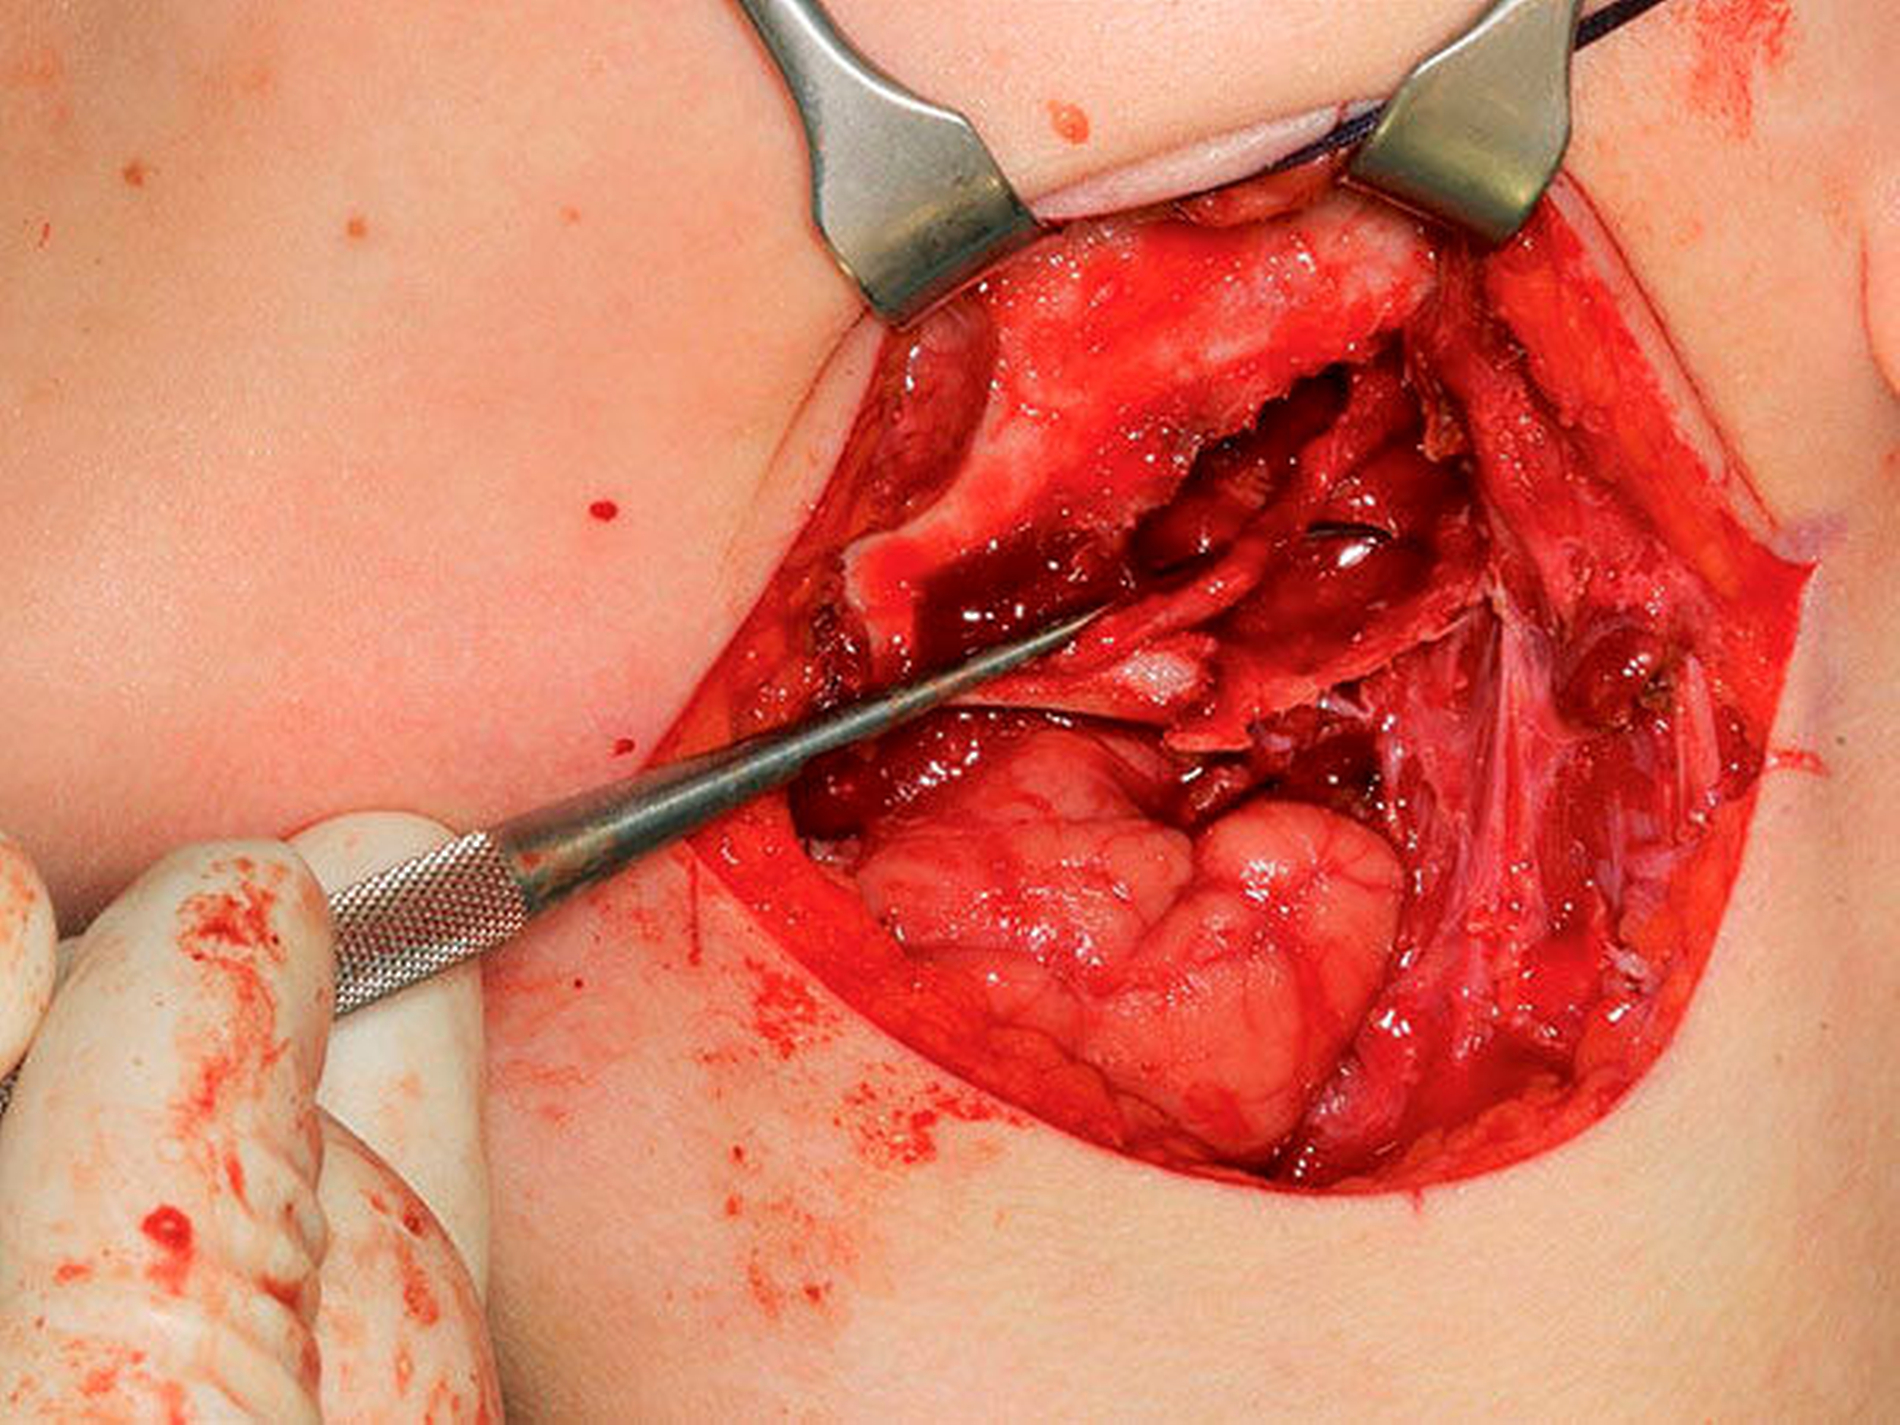

Bei bekannter histologischer Entität wurde ein einzeitiges operatives Vorgehen mit zeitgleicher Exkochleation der Raumforderung im linken Kieferwinkel sowie einer Augmentation durch ein autologes kortikospongiöses Beckenkammtransplantat festgelegt und komplikationslos durchgeführt.